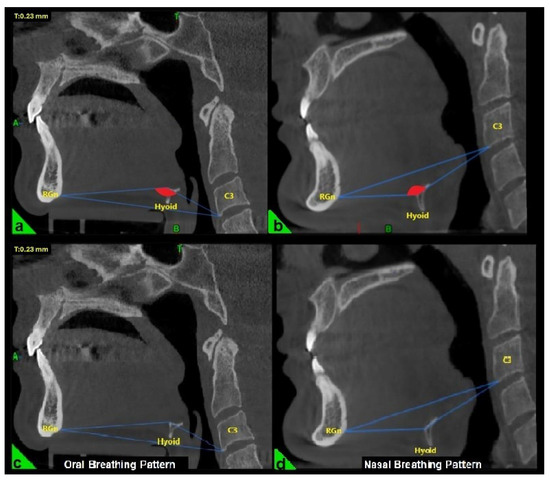

In the three-dimensional cephalometric analysis, three key measurements were performed to evaluate the position and morphology of the hyoid bone. The hyoid angle was defined as the angle formed by two lines: one extending from the anterior-inferior point of the third cervical vertebra (C3) to the most anterior point of the hyoid bone, and the second from this point to the retrognathion (RGn), which is the most posterior-inferior point of the mandibular symphysis (Figure 1a,b) [22].

Figure 1.

Evaluation of the hyoid angle in three-dimensional cephalometric analysis. RGn: Most posterior-lower point of the mandibular symphysis; Hyoid: Center of the hyoid bone; C3: Anterior-lower point of the third vertebra of the cervical vertebra. (a) Negative hyoid angle (b) Positive hyoid angle (c) Oral breathing pattern due to negative hyoid angle (d) Nasal breathing pattern due to positive hyoid angle.

The breathing pattern of each participant was classified as either nasal or oral based on the “hyoid triangle” technique, applied to sagittal CBCT sections using Dolphin 3D software (Dolphin Imaging & Management Solutions®, Chatsworth, CA, USA). Only this method was used to determine the breathing pattern. This method involves constructing a triangle using three anatomical landmarks: the anterior-inferior point of the third cervical vertebra (C3), the most anterior point of the hyoid bone, and the retrognathion (RGn). In this configuration, the RGn–C3 line serves as the base, and a triangle is formed by connecting these three points. When the hyoid bone is positioned above the RGn–C3 plane, the triangle has a superior vertex and is considered a “negative triangle,” indicating an oral breathing pattern (Figure 1a,c). Conversely, when the hyoid lies below the RGn–C3 line, the triangle takes on a “positive” configuration, which is indicative of nasal breathing (Figure 1b,d) [22].